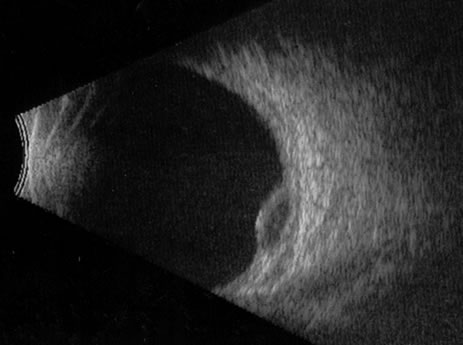

Unfortunately, imaging studies are not always diagnostic. The A- and B-scans shown in Figures 3 and 4 were from a patient with unilateral media opacity referred for evaluation and treatment of a presumed uveal melanoma. Occasionally, if the cataractous lens is scanned tangentially, artifact can occur. A repeat ultrasound at our institution was negative for tumor, and the referral ophthalmologist who performed a cataract extraction noted that no tumor was present and that the patient has an excellent visual outcome. In contrast, the patient shown in Figure 5 was referred with a presumed uveal melanoma with secondary inflammation and a history similar to that described for the patient shown in Figure 111 Ultrasound and CT examinations were not diagnostic. Because the eye was blind and painful, it was enucleated, and an extremely necrotic uveal melanoma was noted histologically. In some necrotic melanomas, the fundus cannot be visualized and the diagnosis cannot be established with imaging studies. Very rarely, a necrotic uveal melanoma can produce sufficient pigment dispersion into the vitreous to obscure the correct diagnosis.12

Fig. 3. B-scan in a patient with dense cataract, showing a possible tumor. Tangential cuts through a cataractous lens can produce a melanoma-like pattern (pseudomelanoma).

Fig. 4. A-scan through the area shown in Figure 3 shows a pseudomelanoma pattern. What distinguished this from a melanoma was a positive-angle kappa (climbing posterior spike). This patient did not have an eye tumor and had 20/20 vision after cataract removal.